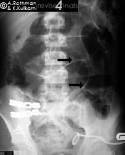

Rigler Sign

See the outline of the small and large bowel outlines - outlined by intraperitonial gas

Free air - Best seen in the right upper quadrant